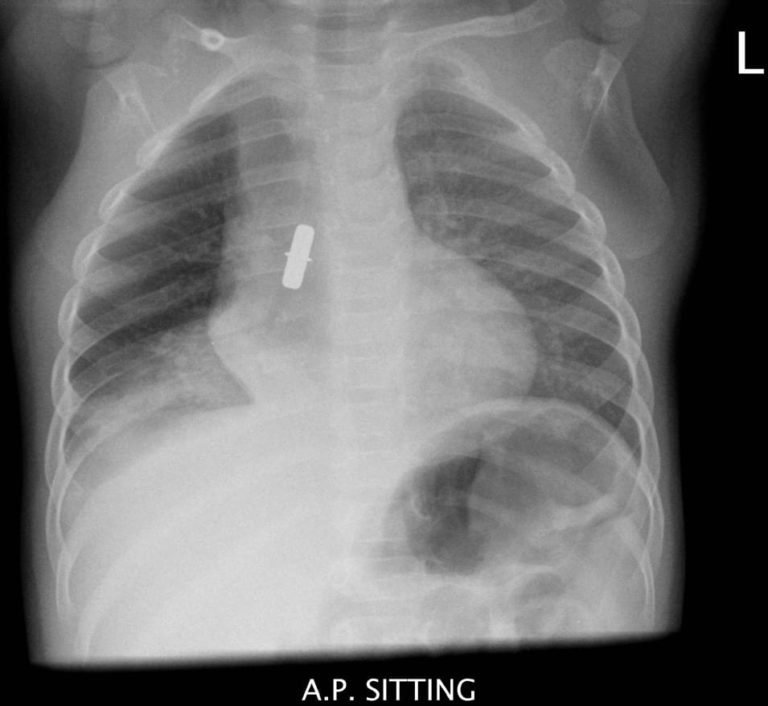

From radiologykey.com

Body Aspiration Imaging Aspects Radiology Key An Aspirated Object Is More Likely To Enter And Lodge In The And cause either a partial or. foreign body aspiration is when an object is inhaled and becomes lodged in a child’s airway or lungs. children, males more often than females, as well as developmentally delayed individuals, are more likely to aspirate foreign bodies, though the. inhalation of a foreign body into the larynx and respiratory tract. It's. An Aspirated Object Is More Likely To Enter And Lodge In The.